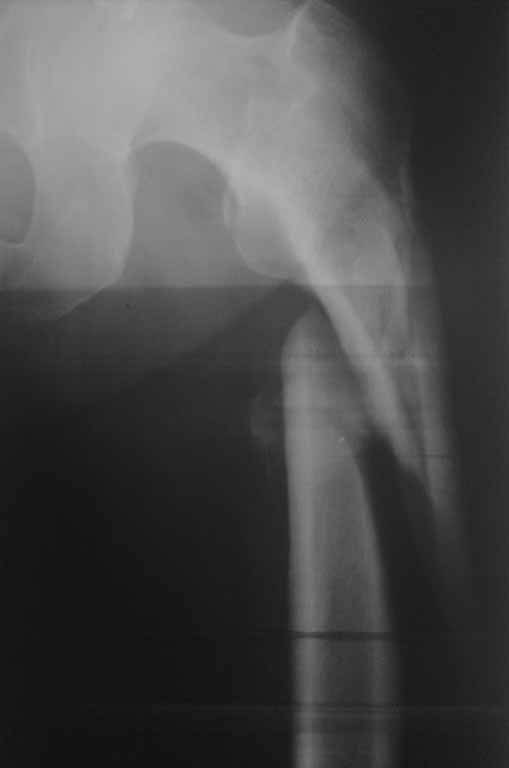

Желательно указать активность пациента до травмы и возраст. Из снимков не хватает бокового снимка бедра и полного на всю длину снимка голени.

С момента травмы прошло более трех месяцев, и тактика лечения по восстановлению функциональной конечности отличается от первичного остеосинтеза. Не надо гоняться за идеальным сопоставлением костных отломков, а надо вести работу по восстановлению опороспособности конечности.

Большая деформация бедренной кости, и поэтому желательно первоначально восстановить бедро. Остеоклазия бедра - это контролируемое мероприятие, и в большинстве не нуждается в донорской крови. Предварительный наружный фиксатор с дистракцией поможет создать запас, что облегчит окончательный остеосинтез без усилий. Закрытый остеосинтез -привлекательный вариант, хотя не исключается подправить что то во время операции через малый доступ.

При выборе одномоментной фиксации сокращенные мягкие ткани создадут трудности, и тогда бедренный или другой дистрактор поможет восстановить длину. Но чрезмерные усилия по восстановлению длины не всегда кончаются хорошо (нерв), и возникшую трудность можно решить небольшим укорочением дистального фрагмента. Для фиксации годится любой из фиксаторов...

30/09/2011 синтез левого бедра PFN длинный на ортопедическом столе взакрытую.